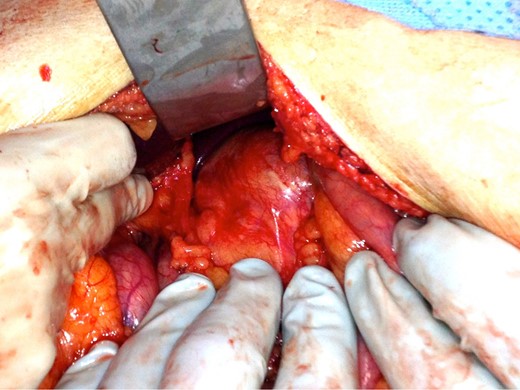

Secondary to the patient’s uncontrolled pain and new CT findings, an exploratory laparotomy was then performed. The mass was found to be adherent to the underlying vasculature, making complete resection impossible (Fig. 2). Given the mass was cystic, it was unroofed, drained and sent to pathology. This revealed a benign LEC of the pancreas (Fig. 3). The patient had an uneventful postoperative course and was discharged home on postoperative Day 6. At 2-week follow-up, the patient was pain free and doing well.